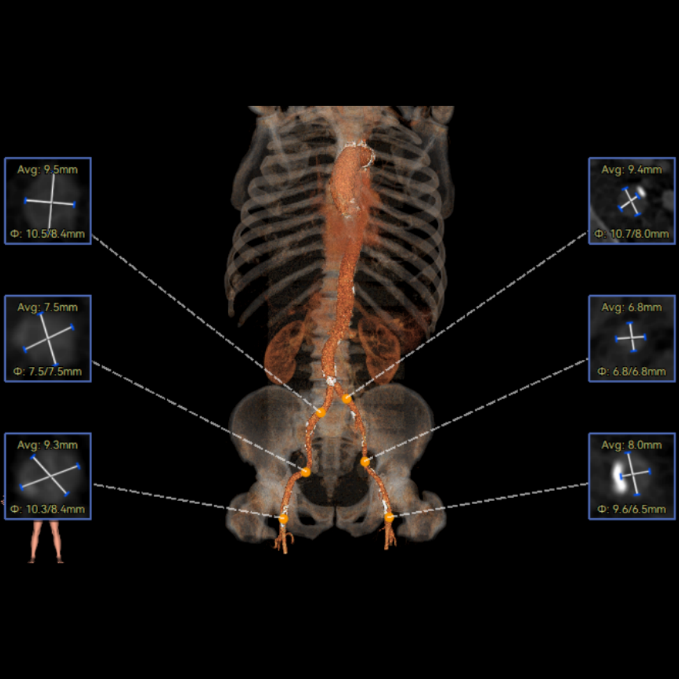

周达新教授 复旦大学附属中山医院 共识引路,干瓣启新,共赴临床解决方案:当前,结构性心脏病的介入治疗已迈入微创化、精准化的新时代。技术的革新、创新器械的上市,都是我们中国技术领跑的印证,《专家共识》的应运而生是中国医生对于行业“规范化”的践行,让治疗更精准、让医者更贴近“以患者为中心”的医疗本质。 潘文志教授 复旦大学附属中山医院 严谨求真重思考 创新临床互验证:在医学的漫长征途中,新器械的突破与严谨的临床研究是两大核心驱动力。拥抱创新的同时需要严谨求证,预装干瓣作为创新器械,其即取即用的特性可以很好的适配“急诊”的场景,此外,国产创新不是简单的复制,干瓣的瓣叶质地不是字面意思“干”的,而具“曲柔性”。所以,需要多看多测,才能全面了解一款产品。《经导管心脏瓣膜治疗术》的问世也是凝结着我们带着临床思维思考的结晶的“独家秘笈”,希望能够将“来时的路”变成未来行业同行者的“高效学习之路”! 患者病史 多病共存陷困境,主动脉瓣狭窄成 “首要威胁” 现病史:患者反复活动后胸闷2年余,无胸痛、心悸,无头晕、晕厥等不适,未予重视。患者轻微体力活动(快走、爬楼梯)即胸闷气促,静息及夜间无不适,无咳嗽、心悸等症状。为进一步诊疗收入我科,患病以来精神、食欲、睡眠、二便及体重均正常。 既往史: 2025年5月7日因小便不畅至外院住院病理穿刺确诊前列腺癌,期间检查心超提示主动脉瓣钙化伴重度狭窄,遂暂缓前列腺手术。2025年05月30日至我院就诊。 2025年5月20日开始服用比卡鲁胺片。患者血脂异常,长期服用丹参滴丸,麝香保心丸,心通颗拉。 手术史外伤史:10年前行肺手术,具体不详。否认外伤史。 入院检查 心电图提示:窦性心动过缓;ST-T改变; 心超显示:主动脉瓣钙化伴重度狭窄及轻度反流,Vmax 4.8m/s、PGmax 93mmHg、PGmean 47mmHg;左房增大,左室壁增厚。 冠状动脉CT造影:左前降支中段浅表心肌桥,主动脉瓣增厚伴重度钙化,主动脉粥样硬化。 术前CT 三叶瓣,中度钙化,主动脉根部直径25.4mm,LVOT直径23.5mm 双侧冠脉开口高度尚可,瓦氏窦尚可,ST尚可,升主尚可,冠脉风险小;中度钙化,心脏角度39.2°;心腔内径可,左室壁增厚。 外周走行尚可,全主动脉存在散在钙化,右侧穿刺点需避开钙化,血管内径可,血管内壁存在纤维增厚。 手术策略:右侧股动脉为主入路,使用20F大鞘;20球囊预扩,植入AV29瓣膜; 手术过程 主动脉根部造影 输送系统柔顺过弓 定位 缓慢释放瓣膜 造影观察 稳定脱钩 最终造影性钙位置良好,轻微瓣周漏 术后超声:轻度瓣周漏,术后平均压差11mmHg 出院前超声:平均压差11mmHg 在多基础疾病患者日益增多的当下,该病例也为临床提供重要启示:针对合并肿瘤、既往手术史的复杂瓣膜病患者,需通过多学科协作(心内科、肿瘤科、麻醉科等)全面评估病情,结合精准影像技术与适配器械,制定个体化手术方案,才能在保障安全的同时,实现最优疗效。 作为中国结构性心脏病领域的标杆学术活动,中国结构周 2025为这类高水平临床病例提供了交流平台,助力推动我国结构性心脏病诊疗技术持续创新,让更多复杂瓣膜病患者受益于精准医疗方案。 ProStyle A®预装干瓣——助力临床最优化解决方案: 轻松过弓,精准可控:该病例全主动脉存在散在钙化,右侧穿刺点需避开钙化,ProStyle A®较细的尺寸+柔顺的输送系统通过性能得到了很好的验证; 平稳释放:平衡的径向支撑力降低了释放过程中的张力,流入端小锥角设计能够迅速锚定贴边; 预装干瓣 便捷顺安:金仕生物专利抗钙化技术运用纳米技术去除组织内的细胞碎片和磷脂,封闭游离醛基,从根本上阻断了瓣膜钙化的多项因素,显著提升了瓣膜的耐久性;同时,相比较传统戊二醛保存方式,干式存储最大限度的保留心包的亲水亲油平衡,还原组织天然曲柔性,进一步保障了瓣叶开合,保证长期耐久性; 专家简介 葛均波 复旦大学附属中山医院(点击查看专家详细简历) 周达新 复旦大学附属中山医院(点击查看专家详细简历) 潘文志 复旦大学附属中山医院(点击查看专家详细简历) · END ·